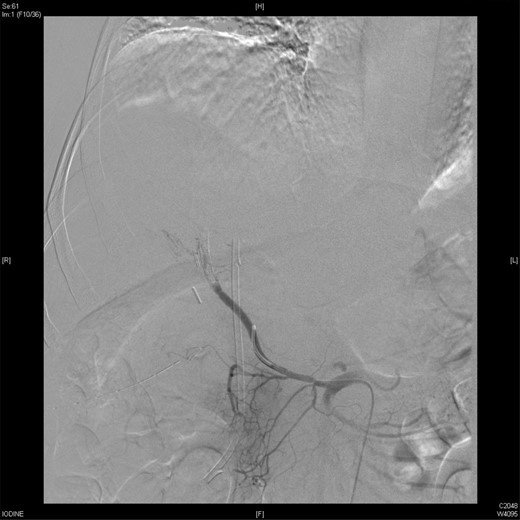

Upon presentation to our center, the patient was febrile (38.9°C) and complained of a left upper limb pain and swelling. The surgical drain was draining a mixture of bile and blood. His WBC count was 14 × 109/l, total bilirubin 35 µmol/l and the direct bilirubin 21 µmol/l. A duplex ultrasound of the upper limb revealed a left brachial vein thrombosis. Hematology was consulted, and a diagnosis of acute upper limb venous thrombosis was established. Owing to the presence of blood in the drain, he was kept on the maximum prophylactic dose of unfractionated heparin. A CT angiography of the abdomen showed two collections, one at the surgical bed near the drain, and the other was subcapsular below the left lateral lobe of the liver, as well as an aneurysm of the replaced right hepatic artery with an active bleeding blush (Fig. 1). The patient was immediately referred for an angiography, which confirmed the CT scan findings (Fig. 2). An arterial stent was inserted at the location of the aneurysm (Fig. 3), and a pigtail drain was inserted to drain any residual collection. An ERCP was also performed, which revealed a Strasberg Class D injury, and a plastic biliary stent was inserted. After the angio-stent insertion and stabilization of the patient, heparin infusion was started. Five days later he developed hematemesis and melena with a significant drop in his Hb to 2 g/l, and his total bilirubin became 183 μmol/l of which 91 μmol/l is direct. A gastroscopy was performed and showed hemobilia (bleeding from the ampulla of Vater). Subsequent angiography demonstrated a leak of contrast just above the arterial stent; hence, a further stent was placed to cover that area of the aneurysm. Similar symptoms reoccurred a week later, and a new angiography showed a new aneurysm from the left proper hepatic artery. A percutaneous thrombin injection of the aneurysm was performed as the bleeding branch was unreached via direct angiography and was filling in retrograde perfusion. During recovery a chest spiral CT was performed, which revealed the diagnosis of a bilateral segmental pulmonary embolism. Heparin infusion with low targets of partial thromboplastin time of 50–60 was started.

A CT scan showed replaced right HAP inside the collection (straight arrow).